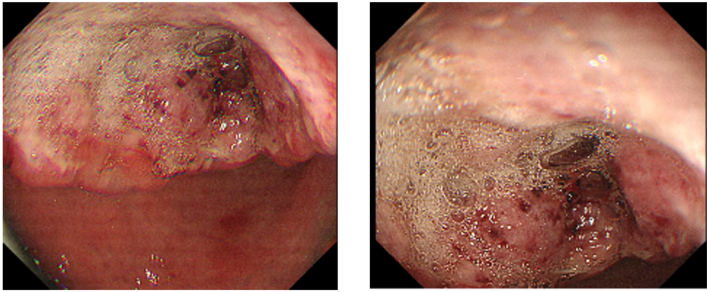

全腹增强CT(2021年8月18日)示:胃窦小弯侧胃壁不均匀增厚伴溃疡形成,考虑胃窦CA;周围见多发淋巴结,部分肿大,考虑转移可能性大。

925.0.png

925.1.png

全腹增强CT

靶病灶

肝总动脉旁淋巴结,短径为47.3mm。